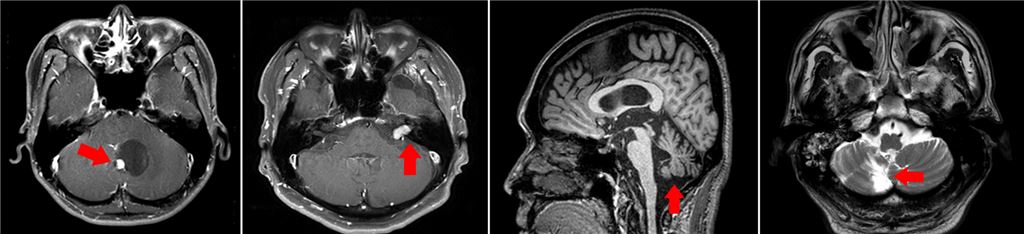

▲중추성 어지럼증을 유발하는 원인 질환 MRI 이미지.[사진제공=분당서울대병원]

[아시아경제 정종오 기자] 어지럼증이 계속된다면 뇌질환을 의심해야 합니다. 어지럼증은 다양한 원인으로 발생합니다. 뇌의 구조적, 기능적 이상에 의해 발생한 어지럼증은 '중추성 어지럼증'에 해당됩니다. 어지럼증을 호소하는 사람들의 4명 중 1명이 뇌졸중, 뇌종양, 퇴행성 뇌질환 등 뇌의 문제로 발생하는 중추성 어지럼증에 속합니다. 문제는 속귀에 위치한 전정기관의 이상으로 인해 생기는 말초성 어지럼증과 증상만으로는 구분이 쉽지 않다는데 있습니다. 이석증 등의 말초성 어지럼증으로 진단 받은 경우에도 증상이 나아지지 않는다면 중추성 원인을 의심해봐야 합니다. 중추성 어지럼증의 주원인이 되는 질환으로 뇌경색과 뇌출혈을 비롯한 뇌졸중, 뇌종양, 퇴행성 뇌질환 등이 있습니다. 이 같은 뇌질환은 진단과 치료시기를 놓치면 심각한 후유증을 남깁니다. 심각한 경우 생명까지 잃을 수 있습니다. 중추성 어지럼증의 대표적 원인질환 중 하나로 뇌졸중이 있습니다. 실제 뇌졸중이 발생하기 전 약 10%의 환자들은 갑자기 어지럽고 비틀거리는 증상을 경험하는 것으로 알려져 있습니다. 어지럼증을 보이는 뇌졸중 환자들은 초기 자기공명영상(MRI) 검사에서 문제를 발견하지 못하는 경우가 20%에 달합니다. 마비 등 눈에 보이는 증상이 나타나는 뇌졸중에 비해 오진 위험이 무려 2배나 높아 주의가 필요합니다. 전정기관을 담당하는 신경에 손상을 입어 발생하는 말초 전정신경염 또한 뇌졸중 전조 현상과 비슷한 급성 어지럼증을 유발하기 때문에 정확한 진단을 위해 자세한 병력청취와 신체검사가 필요합니다.뇌종양이 있는 경우에도 종양이 서서히 자라면서 어지럼증과 두통을 느낍니다. 주로 50대에서 60대에서 많이 발병하는데 최근에는 젊은 층의 유병율도 높아지는 추세입니다. 뇌졸중의 경우 고혈압이나 당뇨가 있는 사람에게서 주로 발생합니다. 반면 뇌종양은 뚜렷한 원인과 예방책이 없어 더 무서운 질환입니다. 퇴행성 뇌질환 환자에게도 지속적 만성 중추 어지럼증이 나타납니다. 초기에는 증상이 경미하고 영상검사도 정상으로 나타나는 경우가 많아 조기에 치료할 기회를 놓치기 쉽습니다. 영상검사가 정상이더라도 눈 운동 장애가 있거나 팔과 다리를 제대로 가눌 수 없는 증상이 함께 나타나는 경우 퇴행성 뇌질환일 가능성이 높습니다. 경미한 어지럼증일지라도 수개월간 지속된다면 자세한 진찰과 검사를 받는 게 좋습니다. 최정윤 분당서울대병원 신경과 교수는 "어지럼증에는 다양한 원인이 있을 수 있는데 서있을 때 중심을 잡기 어려운 자세불안 증상 혹은 두통과 함께 어지럼증이 지속적으로 나타난다면 뇌질환으로 인한 중추성 어지럼증일 가능성이 높다"며 "신속히 병원을 찾아 원인질환을 밝혀내고 치료를 시작해야 한다"고 조언했습니다. 이어 "조기진단과 치료를 통해 후유증을 최소화 할수록 뇌가 회복될 여지가 크고 약물과 전정운동치료를 꾸준히 실시하면 호전될 수 있다"고 덧붙였습니다. 정종오 기자 ikokid@asiae.co.kr<ⓒ세계를 보는 창 경제를 보는 눈, 아시아경제(www.asiae.co.kr) 무단전재 배포금지>